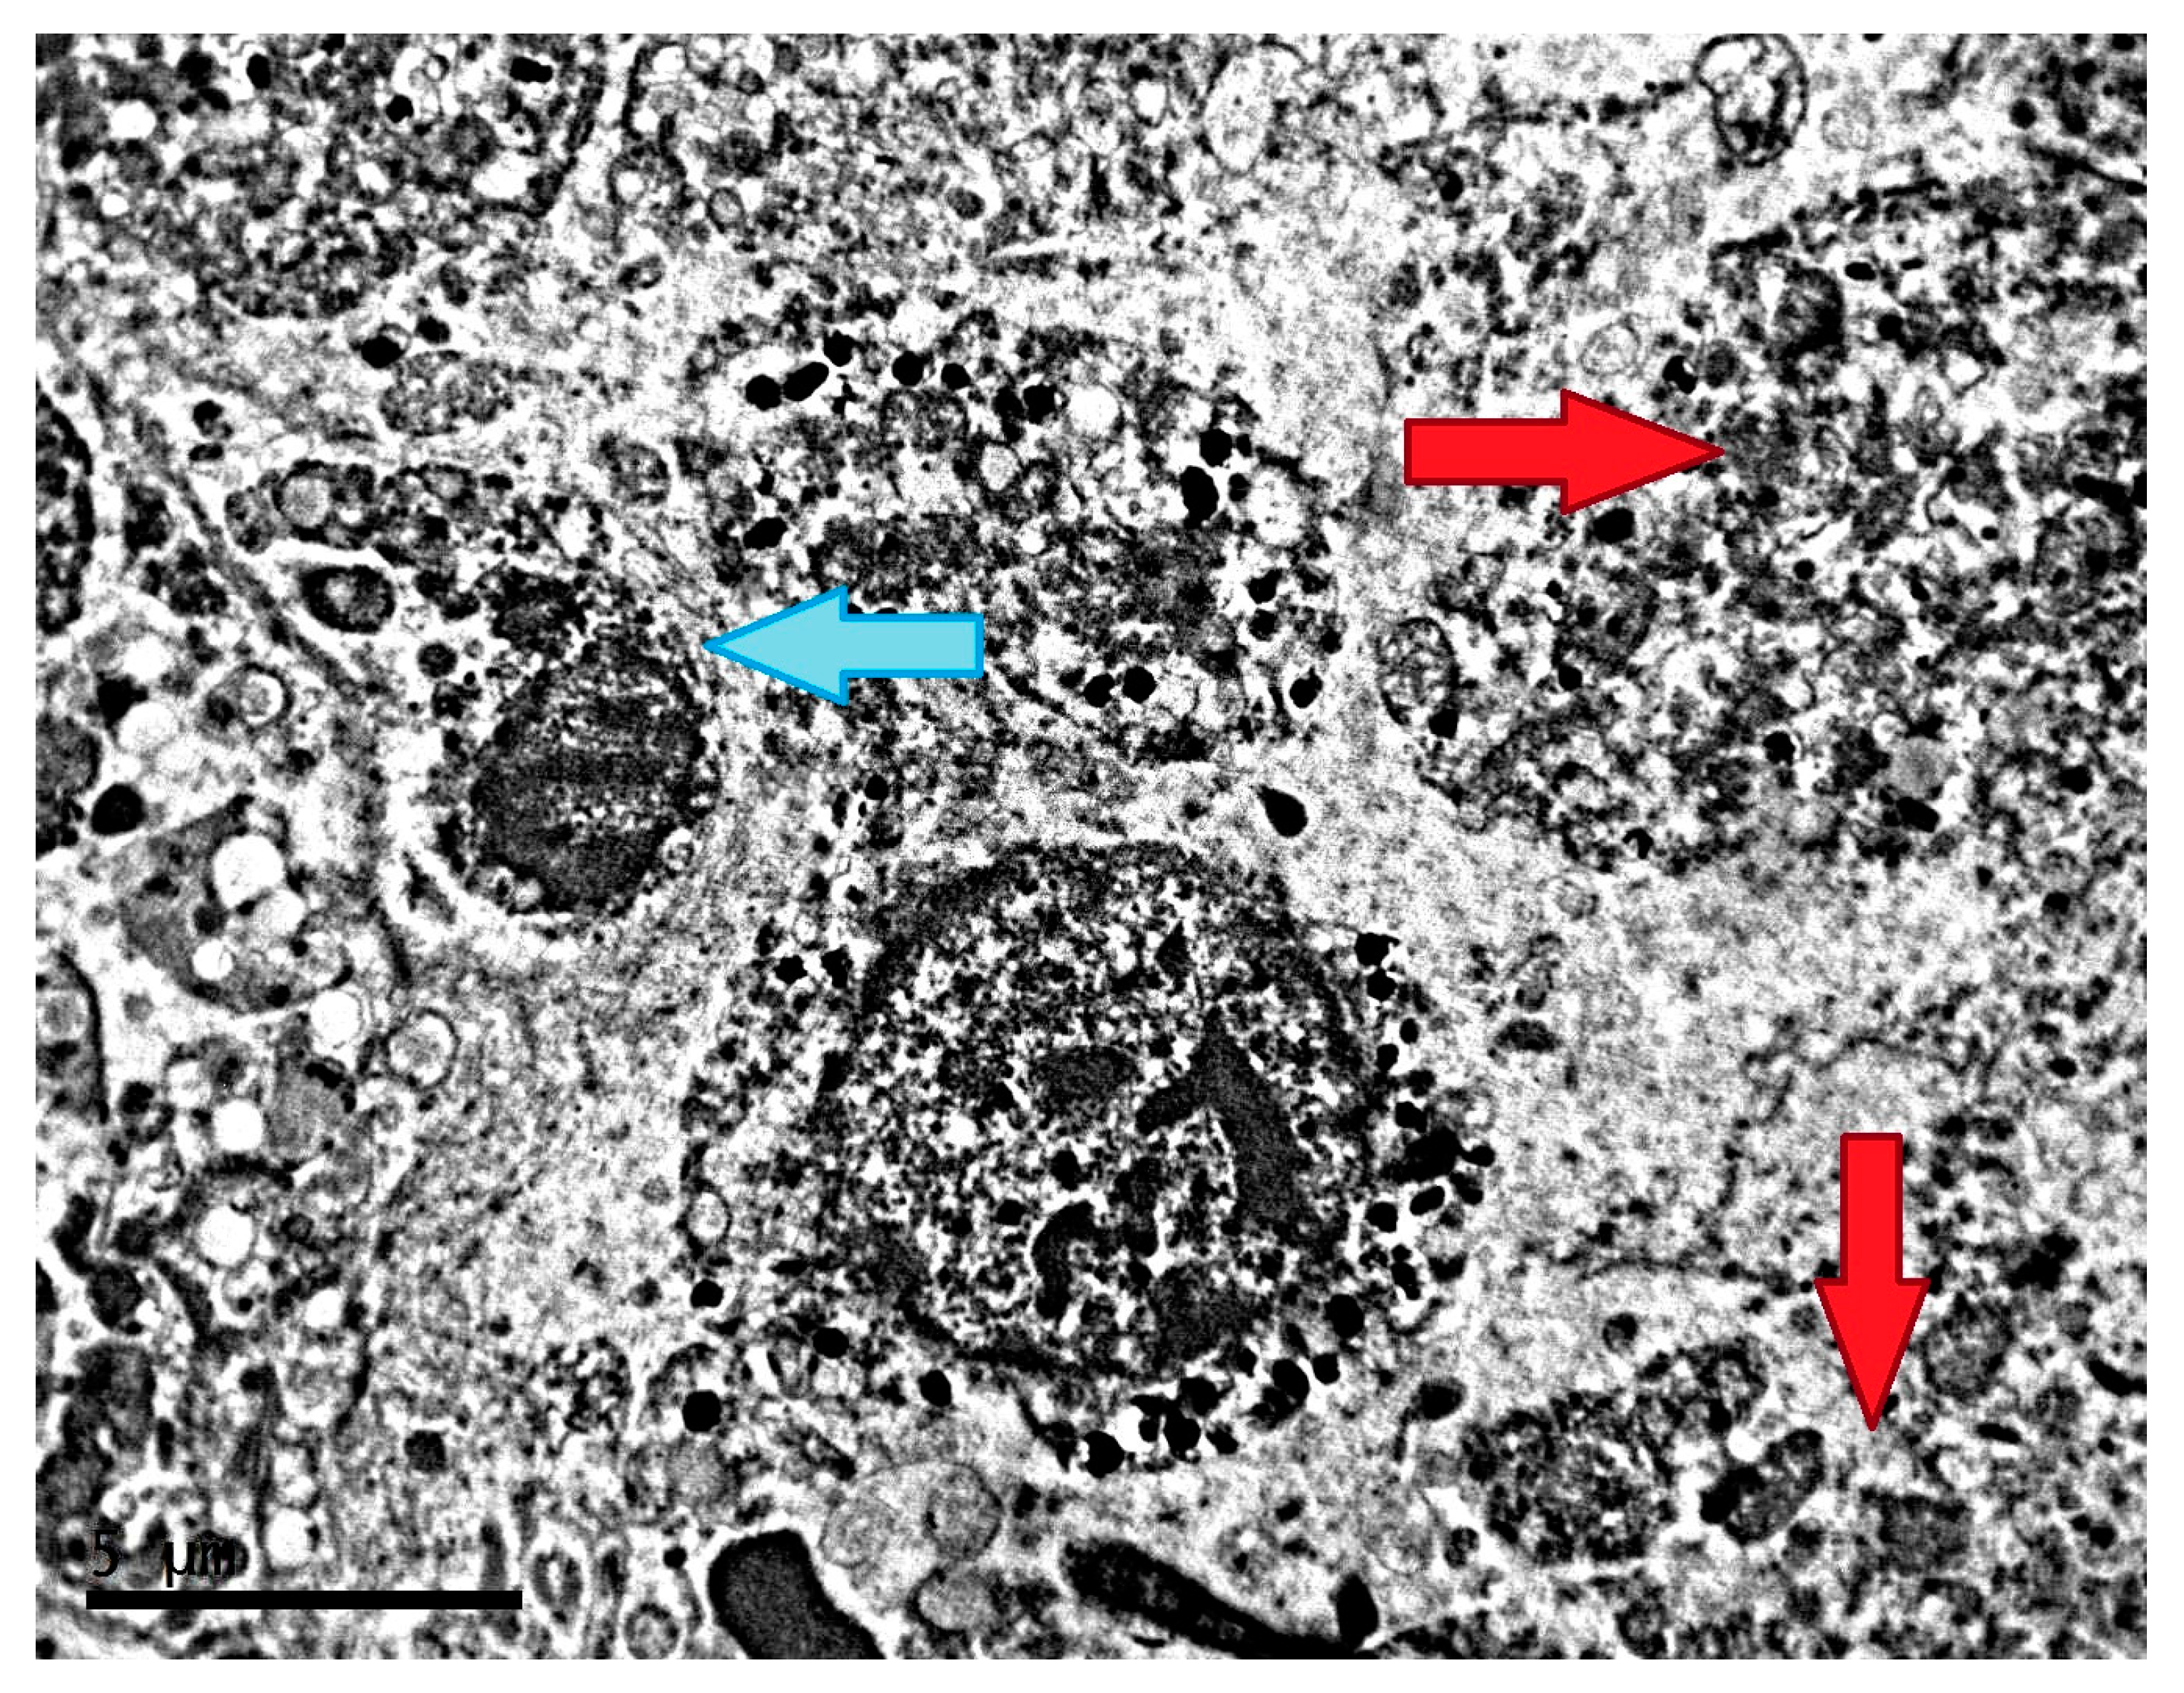

2.2. Ultrastructure of Transplantable Malignant Melanoma B16 in Conditions of Constant Lighting Regime